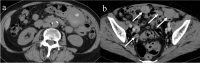

Gastrointestinal stromal tumors (GISTs) originating from the interstitial cells of Cajal in the muscularis propria are the most common mesenchymal tumor of the gastrointestinal tract. Multiple modalities, including computed tomography (CT), magnetic resonance imaging (MRI), fluorodeoxyglucose positron emission tomography, ultrasonography, digital subtraction angiography, and endoscopy, have been performed to evaluate GISTs. CT is most frequently used for diagnosis, staging, surveillance, and response monitoring during molecularly targeted therapy in clinical practice. The diagnosis of GISTs is sometimes challenging because of the diverse imaging findings, such as anatomical location (esophagus, stomach, duodenum, small bowel, colorectum, appendix, and peritoneum), growth pattern, and enhancement pattern as well as the presence of necrosis, calcification, ulceration, early venous return, and metastasis. Imaging findings of GISTs treated with antineoplastic agents are quite different from those of other neoplasms (e.g. adenocarcinomas) because only subtle changes in size are seen even in responsive lesions. Furthermore, the recurrence pattern of GISTs is different from that of other neoplasms. This review discusses the advantages and disadvantages of each imaging modality, describes imaging findings obtained before and after treatment, presents a few cases of complicated GISTs, and discusses recent investigations performed using CT and MRI to predict histological risk grade, gene mutations, and patient outcomes.